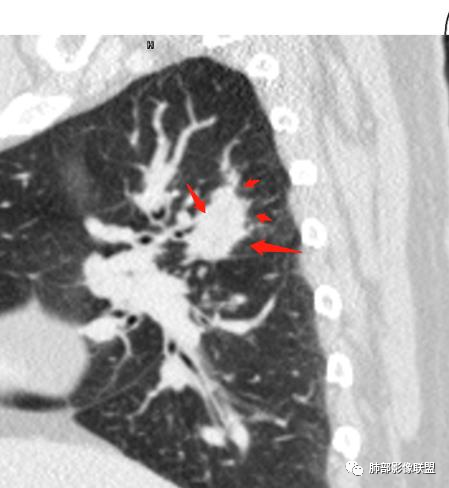

傅昌瑜:女性,咳嗽咳痰痰中带血1月。血常规、肿瘤标记物正常。CT:右上叶后段类圆形结节,内侧紧贴纵隔,前与右主支气管后壁分界不清。外后部分边缘平直收缩、矢状位可见U型凹陷、桃尖征,周围见边缘模糊的GGO,软毛刺。右上叶后段支气管似乎变狭窄。增强呈薄壁环形强化,内部强化不明显,强化时边缘似见有多个小结节与主病灶融合(芋艿子?)。远端见细小结节。整体考虑炎性病变,结核可能性大,注意鉴别腺癌。

马春平(张家港市一院胸外科):结核+1:右上叶后段小病灶大坏死分隔状、临近支气管壁增厚狭窄

岁月:病史:咳痰血1月,右上叶占位,无发热盗汗;女,cea,角蛋白,nse正常影像:右上叶后段,后段支气管略窄,右肺门钙化,该处淋巴结成团,形态可辨认病灶边缘有钙化,周边高密度中间低,密度不均,芋艿子,中心44.6hu,边缘有强化,环状,应该较高。周边有点,平直,无毛刺,像棘角,有轻度牵拉毛刺软,血管推移。诊断:良性结节,结核。

杨泽锋:回顾性分析:周围的晕有一定提示作用

1.女性,咳嗽咳痰痰中带血1月。血常规、肿瘤标记物正常。             2.CT示右肺上叶不规则肿块,边缘以平直收缩为主,可见U型凹陷及桃尖征,周围见边缘模糊的GGO,软毛刺,从形态学的角度病灶更支持炎性改变; 3.增强呈薄壁环形强化,壁光整、清楚,也支持炎性改变;病灶内部平扫CT值密度比较高,约40HU,明显高于水的密度,而且未见强化,提示病灶的坏死可能为凝固性坏死;    4.从上面的分析,病变更符合炎性,患者白细胞不高,治疗后没有好转,不支持普通细菌的感染;影像病灶较局限,边界较清楚,病灶慢性炎症或肉芽肿,形态机发病部位更符合继发性肺结核。患者非易感人群,病灶孤立,尽管有液化,也很难第一时间考虑真菌,尤其是曲霉菌感染。什么是炎性肉芽肿?炎性肉芽肿的常见疾病谱系有哪些?那什么是凝固性坏死和干酪样坏死?跟一般的液化性坏死有什么区别?接下来我们逐一学习一下。